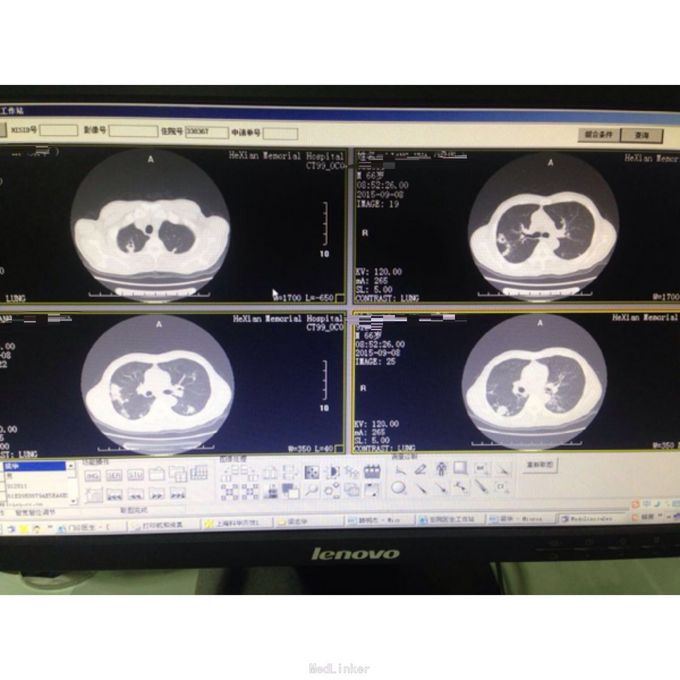

诊断:双肺继发型肺结核并右肺上、下叶及左肺上叶尖后段多发空洞形成 治疗:入院后予吸氧、雾化、抗炎(头孢哌酮/他唑巴坦)、抗结核(异烟肼、利福平、吡嗪酰胺)化痰、控制血糖等治疗,并行支纤镜吸痰,患者症状好转出院。 随诊+讨论:患者规则抗结核治疗1年,血糖控制良好,患者无咳嗽咳痰,无畏寒发热等不适,但复查CT(2015-09-08):1、双肺继发型肺结核大致同前;右肺上叶多发空洞,部分 较前稍增大,建议治疗后复查。2、气管隆突下淋巴结较前缩小。重新阅片:其实双肺病灶与2014-10相比,有所吸收好转。